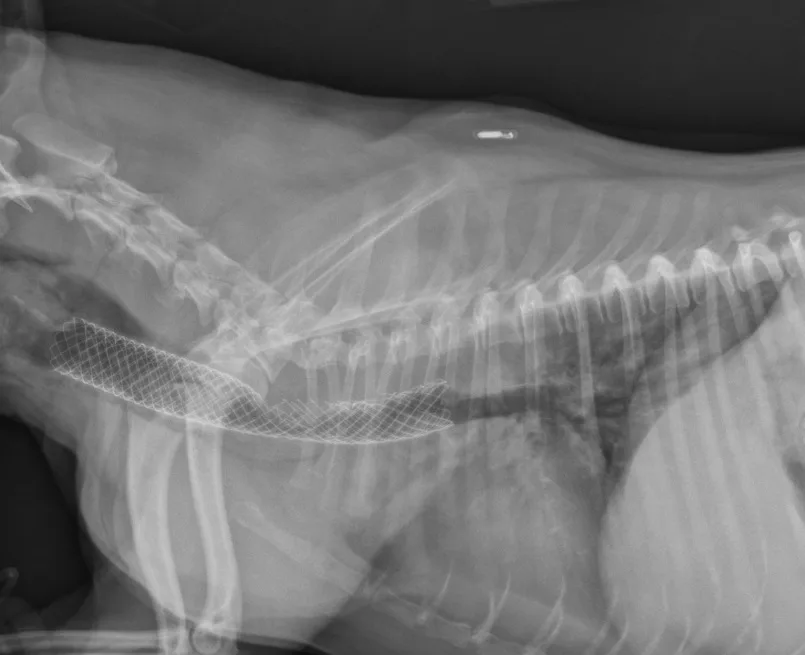

Many surgeons prefer intraluminal stents because they can be noninvasively placed in the cervical or thoracic trachea, reducing risk for complications and shortening anesthetic times. Vet Stent–Trachea is a woven, reconstrainable, self-expanding, nitinol stent3-8 (Figure 3). Nitinol, a nickel–titanium alloy, has thermal shape memory, super elasticity, and elastic hysteresis; the latter minimizes outward force on the interior lumen of the trachea, regardless of stent size.24 The undeployed intraluminal stent is secured within a low-profile delivery system that has radiopaque markers to facilitate positioning. As it is released from the catheter, the stent expands to meet the internal wall of the trachea, foreshortening as it increases in diameter. Because the stent is reconstrainable, it can be pulled back into the delivery system for repositioning after partial release.

Fully deployed stent. Courtesy of Infiniti Medical.

Patients are recovered in an oxygen cage and monitored for signs of respiratory distress. They are sent home on a tapering dose of corticosteroids, 2 weeks of antibiotics, and client instructions to administer sedatives and antitussives as needed. In one study of 18 dogs, the mortality rate was 11.1% within 60 days after stent placement; however, long-term improvement was observed in the remaining dogs.22 Stress, excitement, and exercise need to be limited for 4 weeks. Patients should be reevaluated (ie, examination, survey radiography) at 1, 3, and 6 months procedure. Because the stent initially irritates the airway, coughing is expected but must be controlled to prevent stent fracture (4A, 4B) or granulation tissue formation (4C). Other potentially life-threatening complications include stent migration, tracheal rupture, and collapse of mainstem bronchi or nonstented regions of the trachea. Rare complications include rectal prolapse and perineal hernia.23 Most clients note immediate improvement in quality of life and, despite the progressive nature of the condition, are satisfied with the procedure.

FIGURE 4A

Lateral radiograph of a fractured stent.